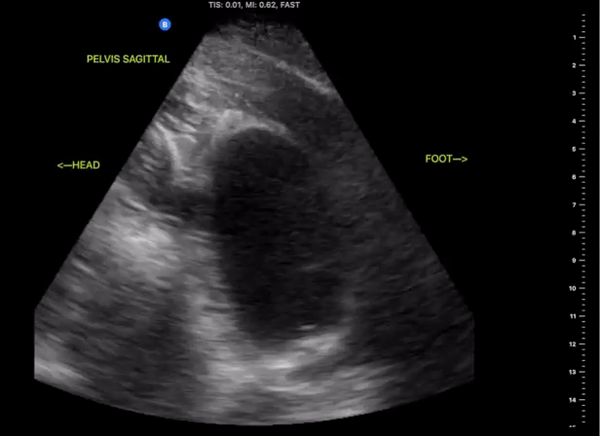

Pelvic Views

Probe/Preset:

Curvilinear / FAST, Abdominal, Bladder

Body Plane:

Transverse and Sagittal

​

Probe Indicator:

-

Transverse: Towards Patient’s Right

Sagittal: Towards Head

Depth:

At least 15cm

Location:

Patient Midline Superior to the pubic symphysis

Identify:

Bladder

Prostate (male)

Uterus/Uterine Stripe (female)

Notes:

Scan through the entire area assessing for the presents of free fluid. The bladder may be difficult to visualize if empty of urine. Small amounts of free fluid in pregnant females are a normal variant.